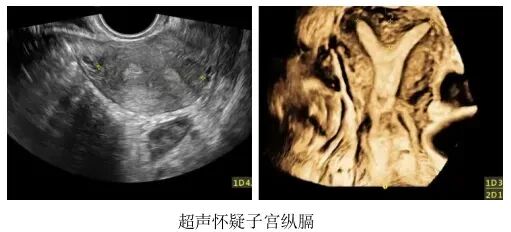

(3)子宫畸形

• 不完全纵膈:则是指这堵墙封的并不完整,还有一半或者一部分,仍保持连通状态。

• 鞍型子宫:是指这堵墙只有地基,并未形成明显的宫腔分隔。

虽然不完全纵膈子宫和鞍型子宫的影响通常小于完全纵膈子宫,但在部分情况下仍可能对生育造成干扰。

一般来说,纵膈越大,就越需要进行宫腔镜手术来修正子宫形态,帮助怀孕。